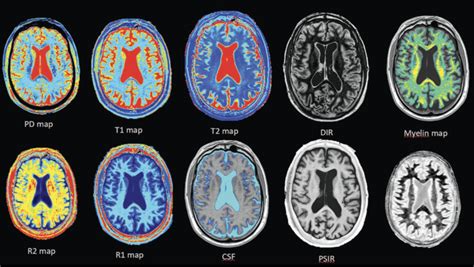

Meth Recovery – Mātai Medical Research Institute

2048×1152

matai.org.nz